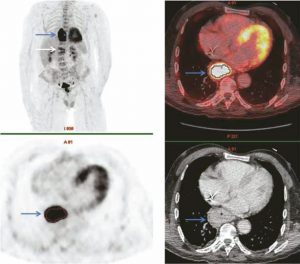

Nous rapportons le cas d’un malade âgé de 80 ans, hospitalisé en août 2016 pour lombalgie aiguë, douleur initialement d’horaire mécanique puis devenue insomniante.